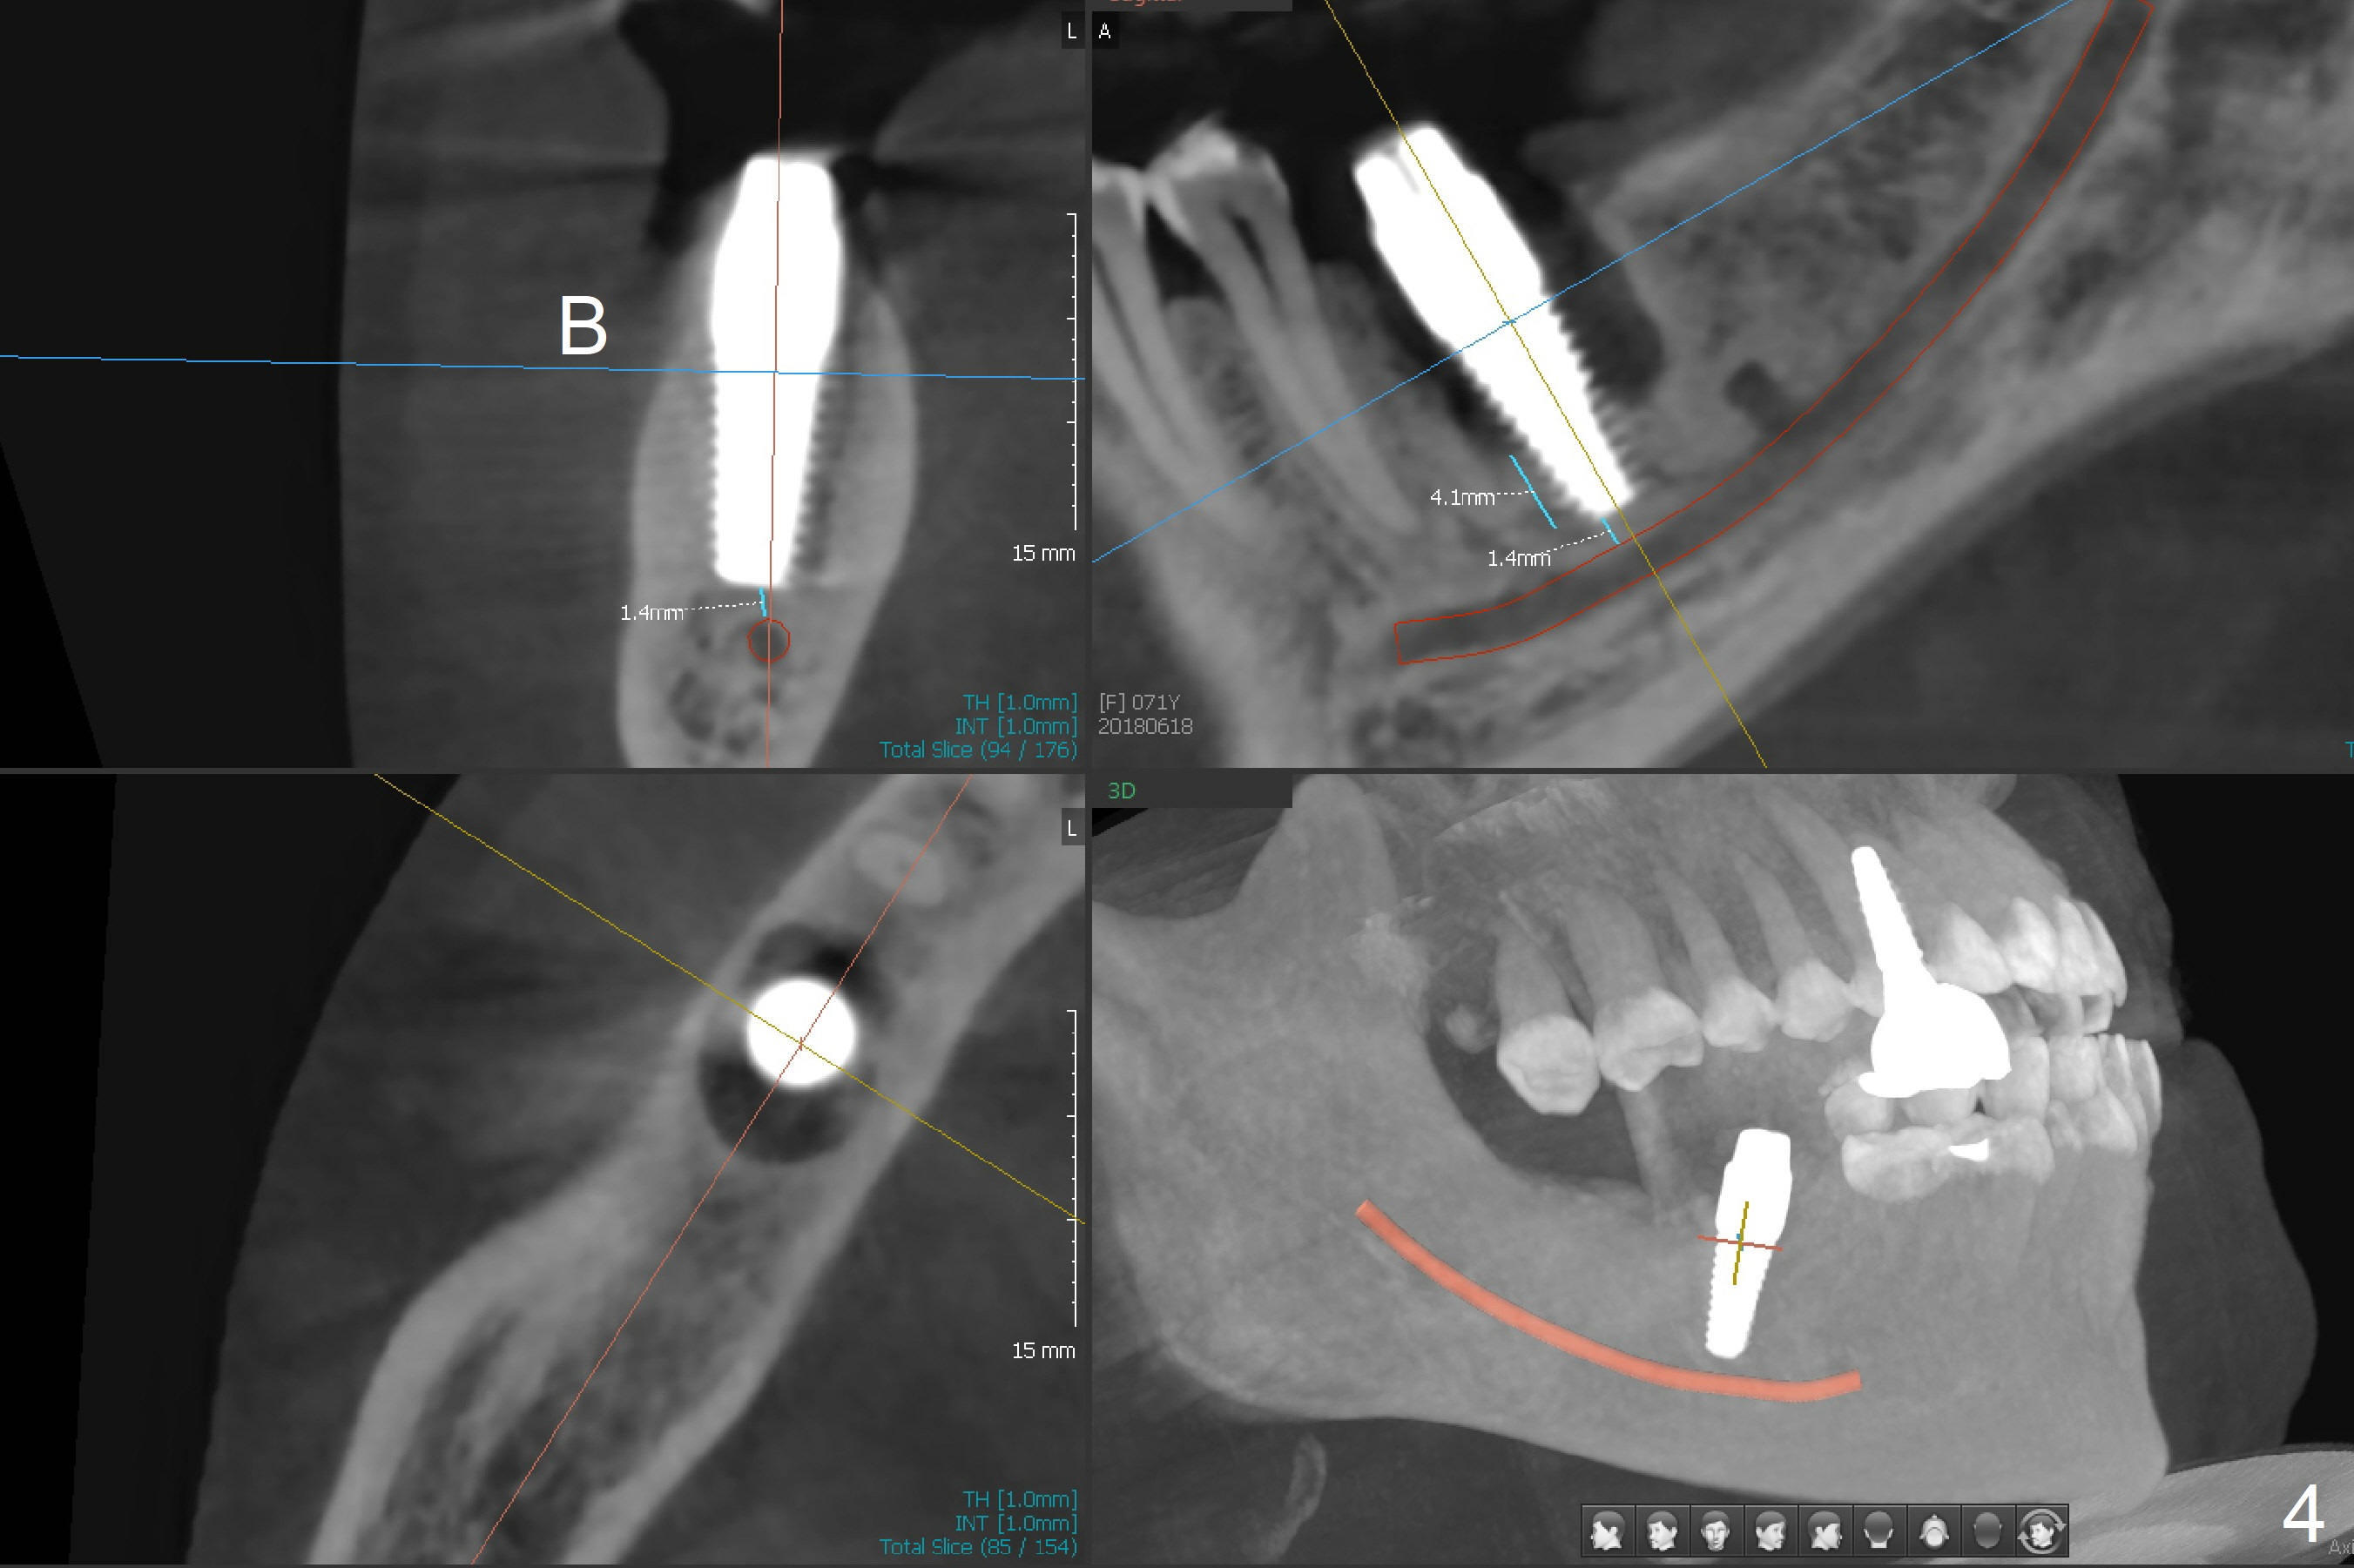

After extraction of the tooth #30 and curettage, the septum becomes so thin that the most coronal portion has to be removed with Rongeur and surgical fissure bur (bone height reduction). Initial osteotomy depth is ~ 4 mm from the flattened septum (Fig.1 (yellow dashed line: apical end of the osteotomy)). Following sequential osteotomy (with intact osteotomy wall), a 6x17 mm tap is placed with apparent clearance from the Inferior Alveolar Canal (Fig.2). When the same size implant is placed with 60 Ncm (Fig.3), the nervous patient feels that the implant is too long (causing pain). CT (Fig.4) and panoramic X-ray (Fig.5) show limited clearance (1.4 mm), but compression of the canal due to high torque could not be ruled out. Since limited amount of the native bone (4.1 mm) for primary stability, the implant is not backed up immediately. Vanilla graft is placed after fabrication of an immediate provisional (Fig.6 *). In brief, immediate implant should be avoided when the septum is thin or the native bone is less than 5 mm (3 mm for primary stability; 2 mm for clearance). In fact the implant has to be untorqued 4-5 times of turn to relieve pain nearly 1 month postop. The patient returns for impression 5 months postop (4 months post implant back up, Fig.7). When the abutment is changed to 5x5 mm and prepared, she reports earache (residual nerve damage?). The patient has had the similar complaint 9 months postop; it appears that there is radiolucency distally (Fig.8 >, as compared to radiopaque mesially (*)). The distal gingiva is tender. With a remade permanent crown, oral hygiene instruction is provided. If necessary, CBCT is taken with possible bone graft.